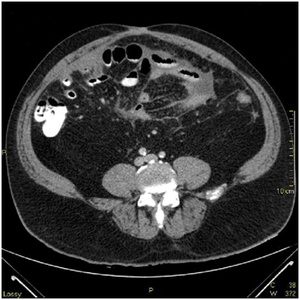

A 56-year-old Vietnam veteran man was admitted with a three-day history of worsening abdominal pain progressing into an acute abdomen. He had past medical history of Hepatitis C, diabetes mellitus, high blood pressure and chronic abdominal pain of unknown etiology. There was no gross bowel pathology by upper endoscopy or colonoscopy early the year of admission.